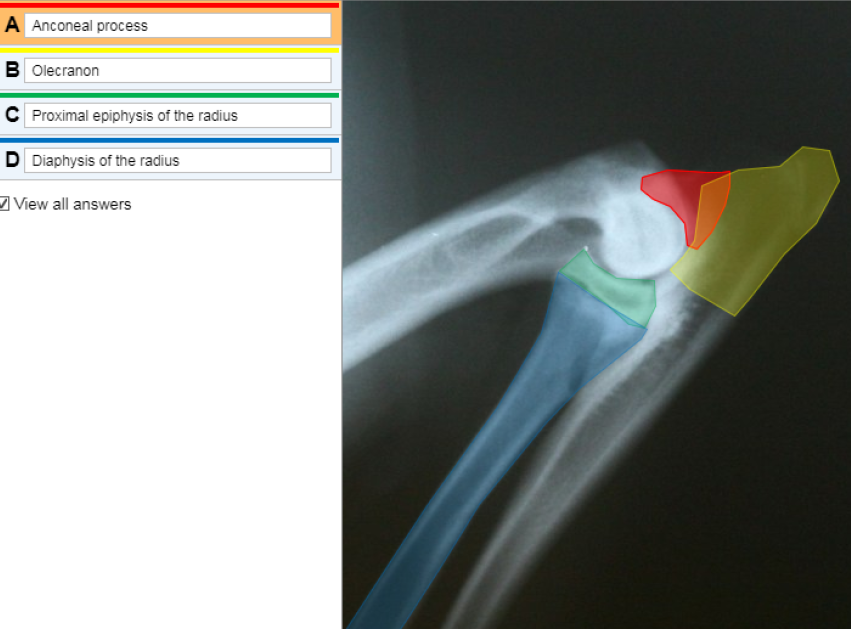

This is a radiograph of a canine elbow.

Identify the following by selecting the appropriate label and placing it on to the midpoint of the correct structure.

Anconeal process

Olecrannon

Proximal epiphysis of the radius

Diaphysis of the radius